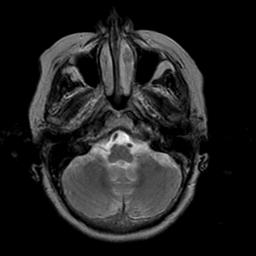

Stroke:T2-weighted MR #2 -- Slice #4

[Home][Help][Clinical] Slice 4